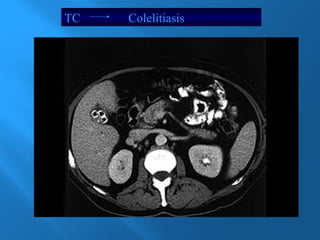

TC Colelitiasis